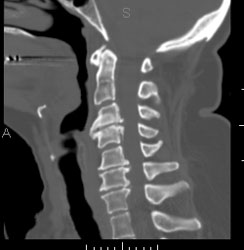

CT-scan va de wervelzuil

ct_cervicale_zuil_reconstructie

Een ct-scan van de wervelzuil wordt in princiepe aangevraagd om letsels ter hoogte van de wervels te beoordelen, of om de doorgangkelijkhdeid van het ruggemergkanaal te controleren.  Den hier aan het opsporen van een discus hernia, of een traumatisch letsel van eenwervel.

Vraagt in principe geen specifieke voorbereiding.

De patiënt gaat op de rug liggen op de onderzoekstafel en moet blijven liggen tot na het onderzoek. Het is hier van belang dat de patiënt niet meer van positie verandert.

Contrast wordt hier in sommige gevallen toegediend, maar dit is geen regel.